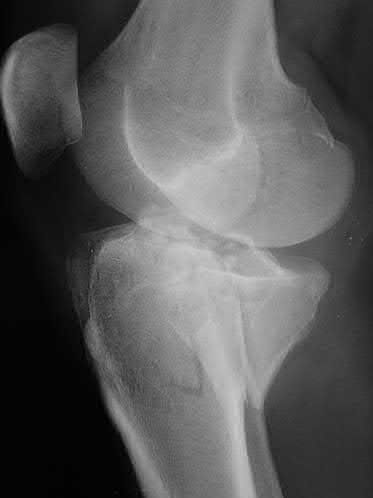

Figure A is an AP radiograph of a posterior knee dislocation. Figure B is a lateral showing the same injury.